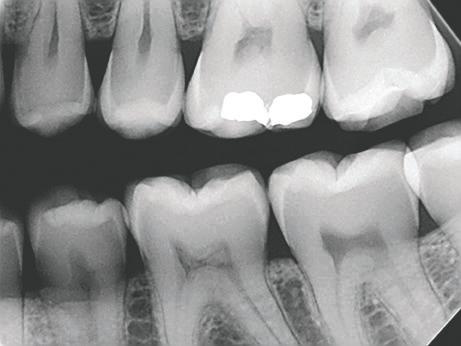

Interproksimal reduksjon, IPR

-30% på hele ContacEZ-serien!

Gjelder til 25.08.2024

Directa ContacEZ IPR er et sett instrumenter laget for å gjøre interproximal reduksjon, IPR, trygt, raskt og enkelt.

Fleksible strips i høykvalitet rustfritt stål, ferdig montert på ergonomisk holder du kan bruke med én hånd. Følger tennenes naturlige konturer, samtidig som de har styrke nok til å lett komme igjennom trange kontaktpunkter. Kan autoklaveres.

IPR Strip System

686,Vnr. 3617

8-pk gul, 0,07mm tykk, 4mm bred. Dobbeltsidig med fint diamantbelegg, taggete.

Directa #32108. Før 980,-

686,Vnr. 3619

8-pk blå, 0,15mm tykk, 4mm bred. Dobbeltsidig, grov diamant, uten tagger. Directa #32508. Før 980,-

IPR PLUS

686,Vnr. 3629

8-pk lilla, 0,25mm tykk, 4 mm bred. Grov diamant, tosidig. Directa #32708. Før 980,-

686,-

3618

8-pk rød, 0,12mm tykk, 4mm bred. Dobbeltsidig, medium diamantbelegg, uten tagger. Directa #32408. Før 980,-

686,Vnr. 3620

8-pk grønn, 0,20mm tykk, 4mm bred. Dobbeltsidig, grov diamant, uten tagger. Directa #32608. Før 980,-

IPR Strip assortert

Ass. pakke med 2 stk gul, 2 stk rød, 2 stk blå og 2 stk grønne.

686,Vnr. 3632

8-pk brun, 0,30mm tykk, 4mm bred. Grov diamant, tosidig. Directa #32808. Før 980,-

Directa #32008. Før 980,686,-

IPR måler

Sett for tykkelsesmåling

0,10 - 0,20 - 0,25 - 0,300,40 og 0,50mm. Autoklavérbar.

Directa #92106. Før 479,-

335,-

Vnr. 3628